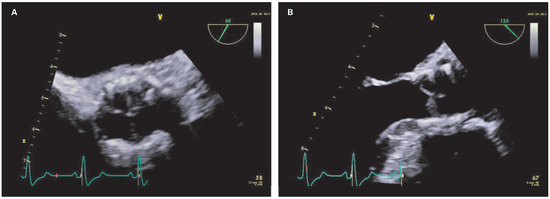

When Apical Is Parasternal, Or "Where Is the Heart?"

by Thilo Burkard and Beat A. Kaufmann

Cardiovasc. Med. 2015, 18(7-8), 226; https://doi.org/10.4414/cvm.2015.00345 - 12 Aug 2015

Viewed by 147

Abstract

A 57-year-old male presented to the medical outpatient department with typical angina pectoris Canadian Cardiovascular Society (CCS) class II and dyspnoea on exertion during the previous weeks [...] Full article

Figure 1